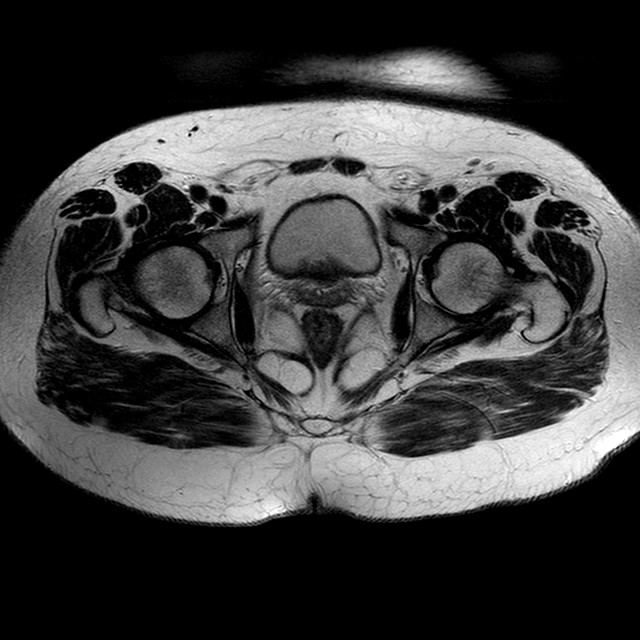

Esami: RMN BACINO

T2w TSE

Evidenti e simmetriche alterazioni osteofitosiche in regione coxo femorale con riduzione delle rime articolari. Degenerazione completa del cercine glenoideo. Non attuali segni di versamento articolare. Non segni di edema osseo che escludono attuale algodistrofia od osteonecrosi. Lieve e simmetrica riduzione del trofismo della muscolatura glutea.